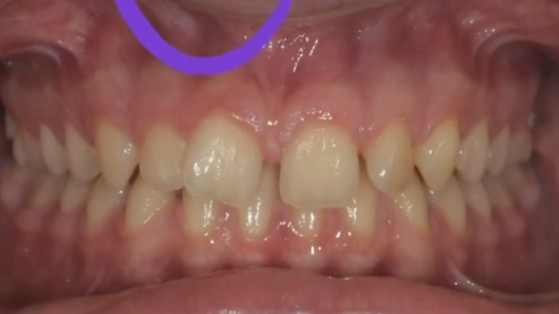

Il diastema, cioè lo spazio tra i denti anteriori, è una caratteristica del sorriso molto visibile e, soprattutto nei più giovani, può diventare una fonte di disagio. Nel video viene presentato il caso di una ragazza di 12 anni con diastema, morso profondo e problemi di chiusura dei denti posteriori, trattata con un approccio ortodontico mirato e con un netto miglioramento in soli 9 mesi.

Nel caso mostrato, la paziente ha 12 anni e presenta uno spazio evidente tra i denti anteriori. Viene sottolineato un aspetto importante: il diastema non è solo una questione estetica.

Una delle cause del diastema descritte nel video è il frenulo labiale con inserzione bassa.

Il frenulo viene descritto come una struttura fibromucosa, simile a una “corda”, che collega il labbro alla gengiva. Quando si inserisce troppo in basso, tra i denti anteriori, crea uno spessore che ostacola meccanicamente l’avvicinamento dei denti.

- il frenulo si inserisce molto vicino ai due denti anteriori;